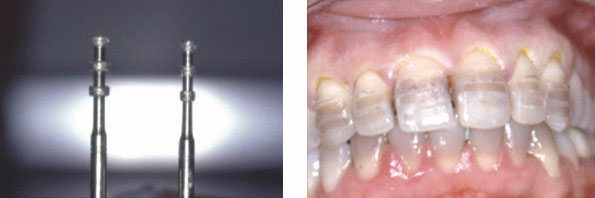

L’utilisation des fraises guides permet de contrôler la profondeur des préparations (fig. 5 et 6 )

Chaque préparation doit assurer une réduction superficielle de 0.3 à 0.5 mm dans l’épaisseur de l’émail. Il faut éviter toute exposition dentinaire dans les régions cervicale et proximale ainsi que tout angle vif résiduel.

Dans le commerce on trouve des coffrets spéciaux qui contiennent des fraises guides et des fraises à congé qui ont la particularité d’avoir dans la même fraise deux granulations différentes (fig.7).